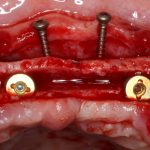

Прежде, чем приступить к аугментации (пластике) лунок зубов, мы подготовили лунки для имплантатов. В таких клинических случаях нет необходимости в использовании шаблона. Вместо этого, мы применяем общепринятые правила позиционирования и соблюдаем рекомендации производителя по хирургическому протоколу:

В процессе ирригации лунки промываются, что позволило нам еще раз подтвердить ранее сделанные выводы. С помощью аналогов имплантатов, входящих в хирургический набор Xive, мы проверили возможность стабилизации имплантатов в будущих лунках. Исходя из правил подбора и позиционирования имплантатов (я очень рекомендую почитать об этом здесь>>) мы остановились на Xive S диаметром 3,4 мм и длиной 13 мм.

Подготовка двух лунок для имплантатов занимает около 10 минут.